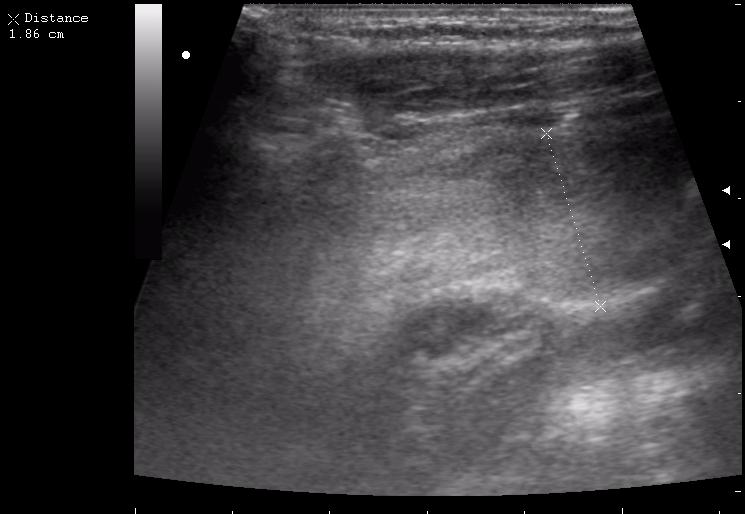

наезд большой черной Прады на маленькую (13кг) 5-летнюю девочку.

получает Медаксон, рабочая версия - изменение желчного пузыря вследствии травмы (шепотом - рекомендация хирургу сменить антибиотик)